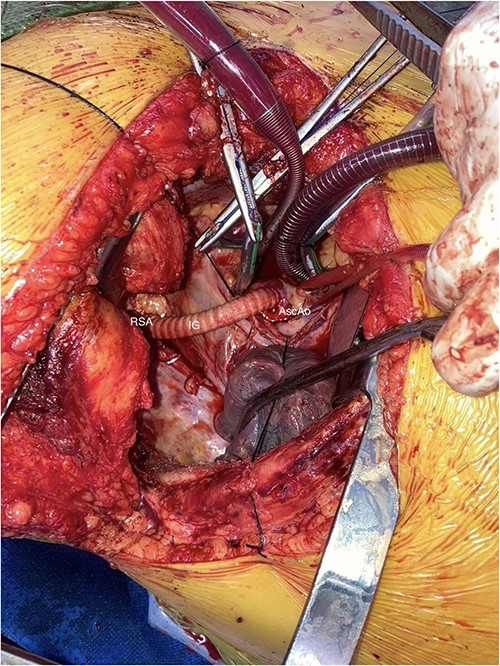

A Covidien vascular stapler was used to divide the aberrant vessel close to its aortic insertion. The vessel was then delivered back behind the esophagus into the right chest. The ARSA was anastomosed (end-to-end) with the Vascutek graft, which had already been anastomosed onto the ascending aorta (Fig. 2).

AscAo: ascending aorta, IG: interposition graft, RSA: right subclavian artery.